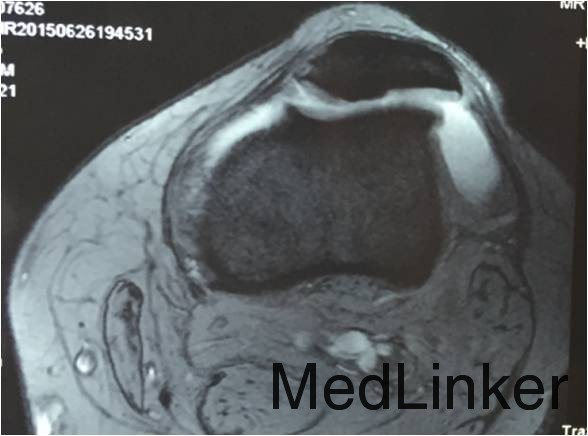

患者男,28岁,因”摔伤致左膝关节髌骨脱位7年余“入院。患者7年前无明显诱因反复出现髌骨脱位,近1个月发生3次脱位。

查体:左膝关节麦氏征(+),浮髌征(+),髌骨加压研磨试验(+),髌骨恐惧试验(±),右膝关节及双上肢未见明显异常。CT及MRI提示:1.左膝关节复发性髌骨脱位;2.左膝关节髌股关节炎。

诊断:1.左膝关节复发性髌骨脱位;2.左膝关节髌股关节炎。拟行左膝关节镜检,关节腔清理,骨赘切除和软骨面修整术。